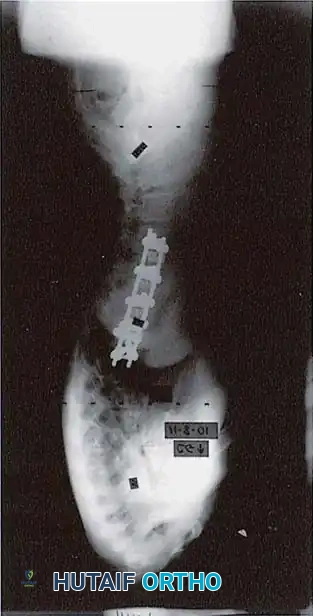

ANTERIOR THORACIC INSTRUMENTATION: A CONTROVERSIAL PARADIGM

The application of anterior instrumentation for primary thoracic curves remains highly controversial. Betz et al. prospectively evaluated anterior spinal instrumentation (using a solid-rod system to prevent the high breakage rates seen with early threaded rods) versus posterior multisegmental hook-rod systems.

Theoretical Advantages of Anterior Thoracic Fusion:

- True 3D Correction: Thorough excision of the intervertebral discs and anulus allows for superior derotation.

- Shorter Fusion Constructs: Fusion from end-vertebra to end-vertebra often saves distal motion segments, reducing the need to cross the thoracolumbar junction.

- Prevention of Crankshaft Phenomenon: By fusing the anterior column in skeletally immature patients (Risser 0), continued anterior spinal growth is arrested, preventing late rotational deformity.

- Sagittal Profile Control: The surgeon can induce either kyphosis or lordosis at specific segments via structural grafting and rod contouring.

Disadvantages and the Shift to Posterior Pedicle Screws:

Despite these advantages, the anterior thoracic approach disrupts the chest cage, negatively impacting pulmonary function tests (PFTs). Furthermore, the thoracic vertebral bodies are small, leading to less secure screw fixation.

Potter et al. definitively compared curve correction between posterior thoracic pedicle screws and anterior single-rod instrumentation in Lenke Type 1 curves. Their findings revolutionized modern practice: Posterior pedicle screw instrumentation provided superior coronal correction, better control of thoracic torsion, and excellent spontaneous correction of uninstrumented lumbar curves. Consequently, anterior instrumentation for thoracic curves is now rarely indicated in contemporary deformity practice.